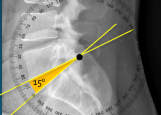

Q what is the name of this measurement? and what is the average + range?

A: Sacral Inclination

assesses the angle of the sacrum relative to a vertical line. The average is 46°, with a range of 30-72°.